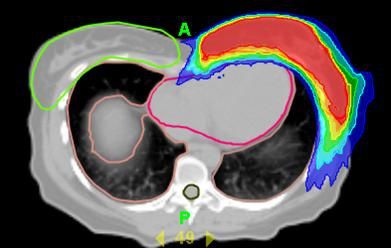

Nach Empfehlung der DEGRO (der Fachgesellschaft für Strahlentherapie in Deutschland) kommt aktuell zur Verkürzung der Strahlentherapie unter anderem der simultan-integrierte Boost (SIB) in Frage. Bei diesem simultan-integrierten Boost wird die zusätzliche Bestrahlung des Tumorbettes (also dort wo der Tumor war), die bisher erst nach der Strahlentherapie der ganzen Brust erfolgte, bereits auf die einzelnen Termine bei der Strahlenbehandlung der ganzen Brust verteilt. Es wird also dieses Boostvolumen bei jeder Fraktion der Brustbestrahlung mit einer geringen zusätzlichen Dosis bestrahlt. Voraussetzung für die simultan-integrierte Boost-Technik sind moderne Bestrahlungs- und Planungstechniken. Die Gesamtbehandlungszeit beträgt fünf bis fünfeinhalb Wochen, also kann damit die Behandlungszeit um etwa 1,5 bis 2 Wochen verkürzt werden. Dabei haben die durchgeführten Studien gezeigt, dass diese Behandlungsart sicher ist, also dass nicht mit mehr Nebenwirkungen zu rechnen ist.